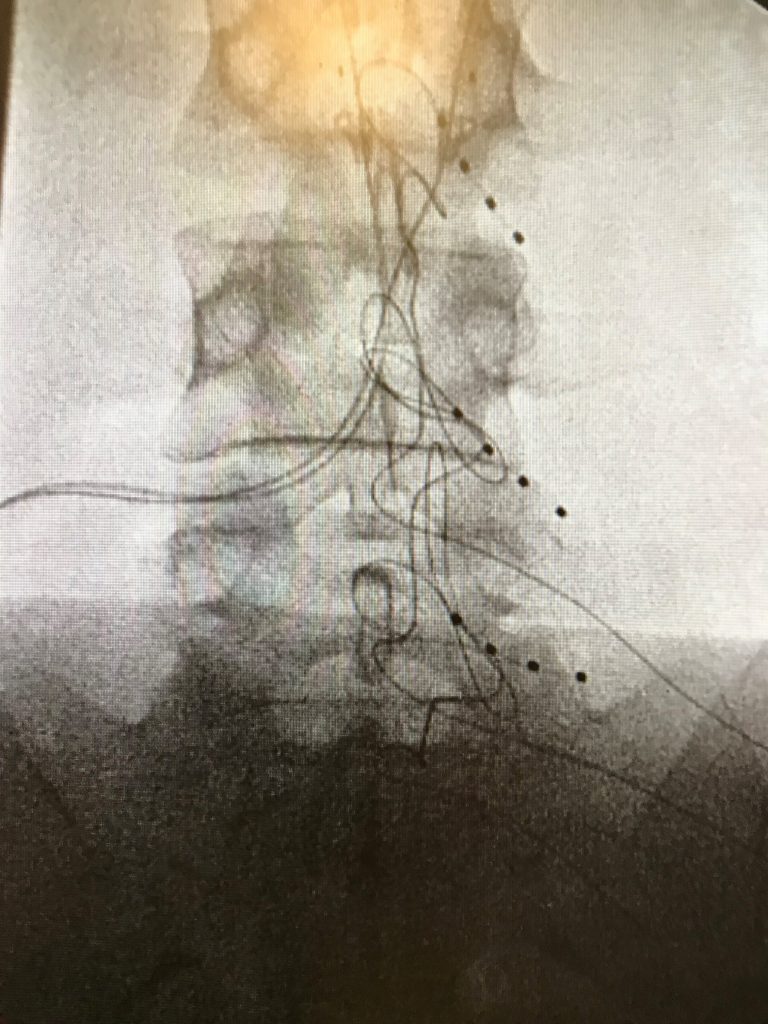

Not all superheroes wear capes. I was diagnosed with complex regional pain syndrome (CRPS) 4 years ago. When I met Dr. Semih Gungor my pain was debilitating. I couldn’t sleep, walk without a cane, and frequently had pain induced vomiting.

Since then Dr. Gungor has given me my quality of life back twice. His determination & compassion made me feel confident he would find the answer to controlling my severe pain. He has a way of making you feel like you are his only patient. He helped me better understand CRPS, and extensively explained treatment options. His clinical knowledge and bed side manor raises the bar. I’m so grateful for all of the help Dr. Gungor and his team provided over the years.